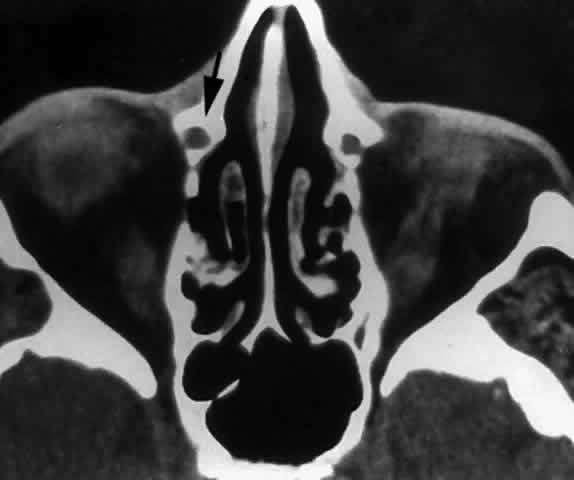

The Nasolacrimal Canal

The nasolacrimal canal is a short, bony tube extending inferiorly, laterally, and posteriorly from the lacrimal fossa toward the inferior meatus of the nose. It contains the membranous nasolacrimal duct. The maxillary bone forms the anterior, lateral, and posterior walls of the canal. The medial wall of the nasolacrimal canal is formed superiorly by the descending process of the lacrimal bone, which articulates with the ascending processing of the inferior turbinate bone below. In some cases, the medial wall of the nasolacrimal canal is almost entirely formed by the maxilla (Fig. 29), with a corresponding decrease in contribution from the lacrimal and inferior turbinate bones. This results in a narrowing of the nasolacrimal canal and corresponding nasolacrimal duct.29

Fig. 29. In this computerized tomographic scan of the orbit, the medial wall of the nasolacrimal canal is almost entirely formed by the maxilla (arrow).

The caliber, length, and course of the nasolacrimal canal vary considerably. The canal is slightly oval, having the greatest dimensions in the anteroposterior plane. The length of the canal is 12 to 13 mm with a slightly lateral convexity. The canal inclines posteriorly (Fig. 30) approximately 15° from vertical as the canal descends from the lacrimal fossa to the nose.28 Clinically, the lateral descent of the nasolacrimal canal can be estimated by drawing a line between the tear sac and the ala nasae. Persons who have narrow interorbital distances and wide noses have the greatest lateral descent, whereas those with wide interorbital distances and narrow noses show a more vertical descent.1,2